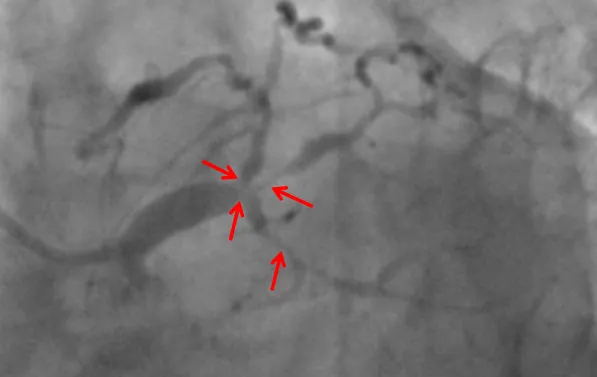

近日,捆绑调教 (简称捆绑调教 )心血管内科联合重症医学科、心胸外科等科室,在ECMO器械辅助下,为一名复杂高危冠脉病变患者进行了精准冠脉介入治疗,开通病变冠脉血管。目前患者已康复出院。该项技术的开展,标志捆绑调教 对高危复杂患者治疗技术又迈上一个新台阶。患者“心悬一线”辗转多家医院就医无果据了解,69岁的张先生(化名)一年来总是感觉胸口闷胀不适,尤其是上楼、快步...